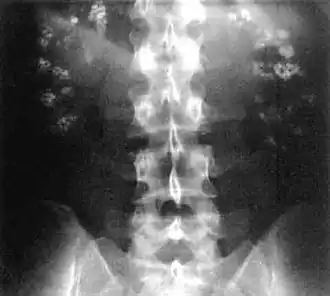

| Bilateral nephrocalcinosis seen on an abdominal x-ray | |

Nephrocalcinosis, once known as Albright's calcinosis after Fuller Albright, is a term originally used to describe the deposition of poorly soluble calcium salts in the renal parenchyma due to hyperparathyroidism. The term nephrocalcinosis is used to describe the deposition of both calcium oxalate and calcium phosphate.[1] It may cause acute kidney injury. It is now more commonly used to describe diffuse, fine, renal parenchymal calcification in radiology.[2] It is caused by multiple different conditions and is determined by progressive kidney dysfunction. These outlines eventually come together to form a dense mass.[3] During its early stages, nephrocalcinosis is visible on x-ray, and appears as a fine granular mottling over the renal outlines. It is most commonly seen as an incidental finding with medullary sponge kidney on an abdominal x-ray. It may be severe enough to cause (as well as be caused by) renal tubular acidosis or even end stage kidney disease, due to disruption of the kidney tissue by the deposited calcium salts.

- Macroscopic nephrocalcinosis: Occurs when calcification can be seen through X-ray imaging.[1]